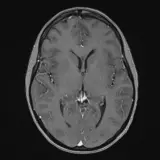

Neuro Fellowship — a course tailored for fellows and practicing radiologists with in-depth reviews of advanced neuro topics like brain tumors, featuring rare diagnoses, differentials, and clinical pearls.

Casos totalmente interactivos con las herramientas que esperaría de un PACS: scroll, ventana, zoom, pan, mediciones, ROI y modo de pantalla completa.

Desplace, arrastre, ajuste ventana y amplíe como en una estación PACS de trabajo